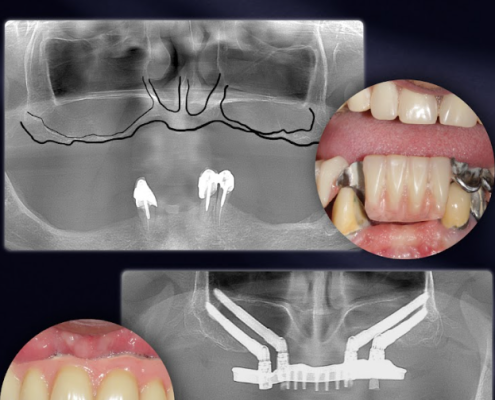

Implants Zygomatiques :

La Réponse Prédictible aux Atrophies Extrêmes

Lorsque le maxillaire ne suffit plus, les reconstructions lourdes ne sont plus une fatalité.

Les implants zygomatiques Southern Implants offrent une alternative éprouvée, prédictible et spécialement conçue pour transformer le pronostic des patients présentant une atrophie sévère.

Pensée pour contourner les déficits osseux majeurs, cette approche permet d’ancrer solidement la réhabilitation dans l’os zygomatique, offrant ainsi une stabilité immédiate, même dans les situations où les implants conventionnels sont impossibles.